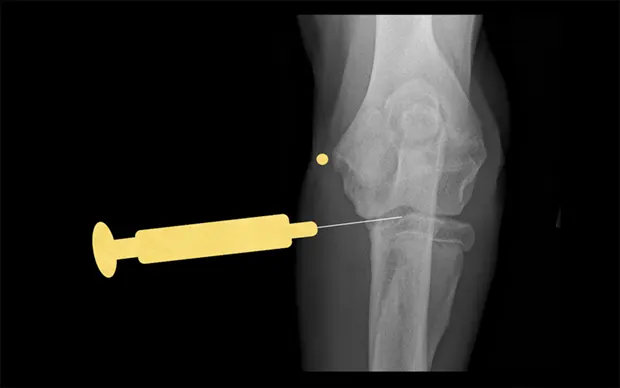

Elbow

With the patient in lateral recumbency and the affected elbow downward, place a rolled towel beneath the elbow. Apply valgus stress on the joint over the towel to open the medial side of the elbow. For large-breed dogs, insert the needle 1.5 cm distal to the medial epicondyle in a medial-to-lateral direction. The caudolateral pouch of the joint is an alternate site; however, marked effusion must be present for successful arthrocentesis.

Craniocaudal view of elbow. Insert needle about 1.5 cm distal to the medial epicondyle (yellow dot) in large-breed dogs.